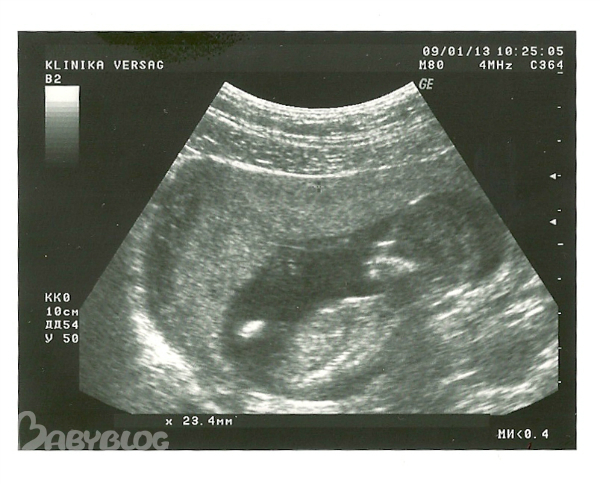

УЗИ 1 скрининга 13 недель

Результаты: УЗИ, КТГ, доплера, скринингаПриветики, девочки! Была сегодня на УЗИ первого скрининга, делала в платной клинике, в моей ЖК на январь мест нет. Врач все подробно рассказала, у нас все хорошо - и пальчики видели и все ручки-ножки, слушали сердечко, показали желудок и мочевой пузырь. По М срок 12нед и 7дн, по УЗИ на 2 дня больше ))))) КТР 62мм, БПР 25мм, ТВП 1,4мм, носовая косточка есть, даже на фото в профиль видно. Врач смотрела долго, малыш активный, долго крутился, хотела сфотографировать красиво, сказала, скорее всего мальчик, между ножек точно что-то есть ))))) посмотрите на фото, может тоже кто-то разглядит мужскую писюльку ))) у нас с мужем радости полные штаны

мы были на УЗИ в 14+5 недель, и между ножек у нас гладко было - у вас точьно мальчик, если сравнить с нашим УЗИ... и я теперь смотря на фото вашего масика перестала сомневаться, что не видать мне писюньчика))

На этом сроке "спереди" мальчики и девочки выглядят одинаково: у обоих "что-то" есть))) Разница у них только при виде сбоку на это самое место.

Да, на этом сроке у них там все одинаково, у девочек клитор, по размеру такой же как и писюн у мальчиков, отличается, только угол наклона, этого самого отросточка, если хорошее оборудование и отличный узист, то мог и не ошибиться))